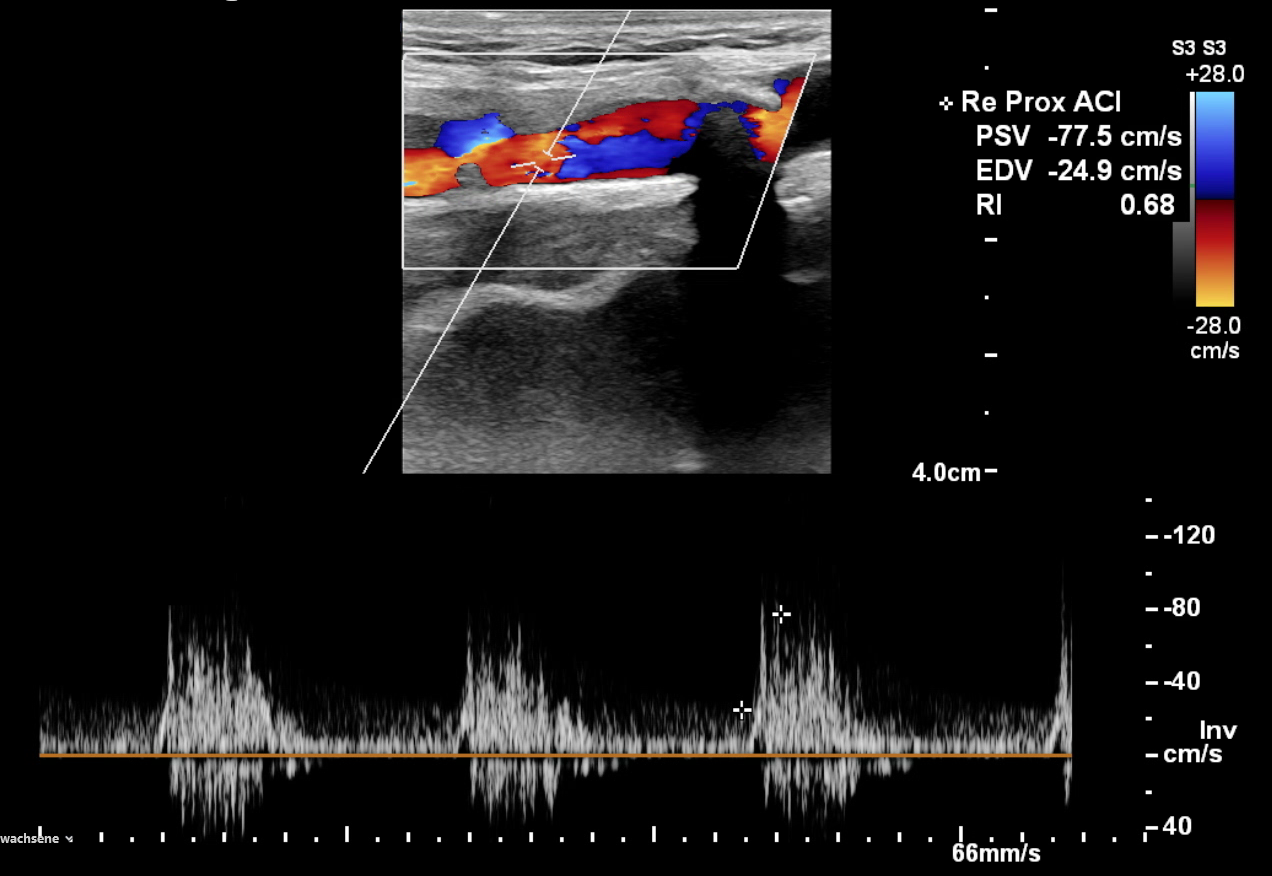

Das erste diagnostische Fenster zeigt den Blutfluss in Echtzeit. Die farbliche Darstellung (Farbduplex) erlaubt es uns, Turbulenzen sofort zu erkennen.

ℹ Der weiße Pfeil im Bild korreliert exakt mit dem Ultraschallbefund.